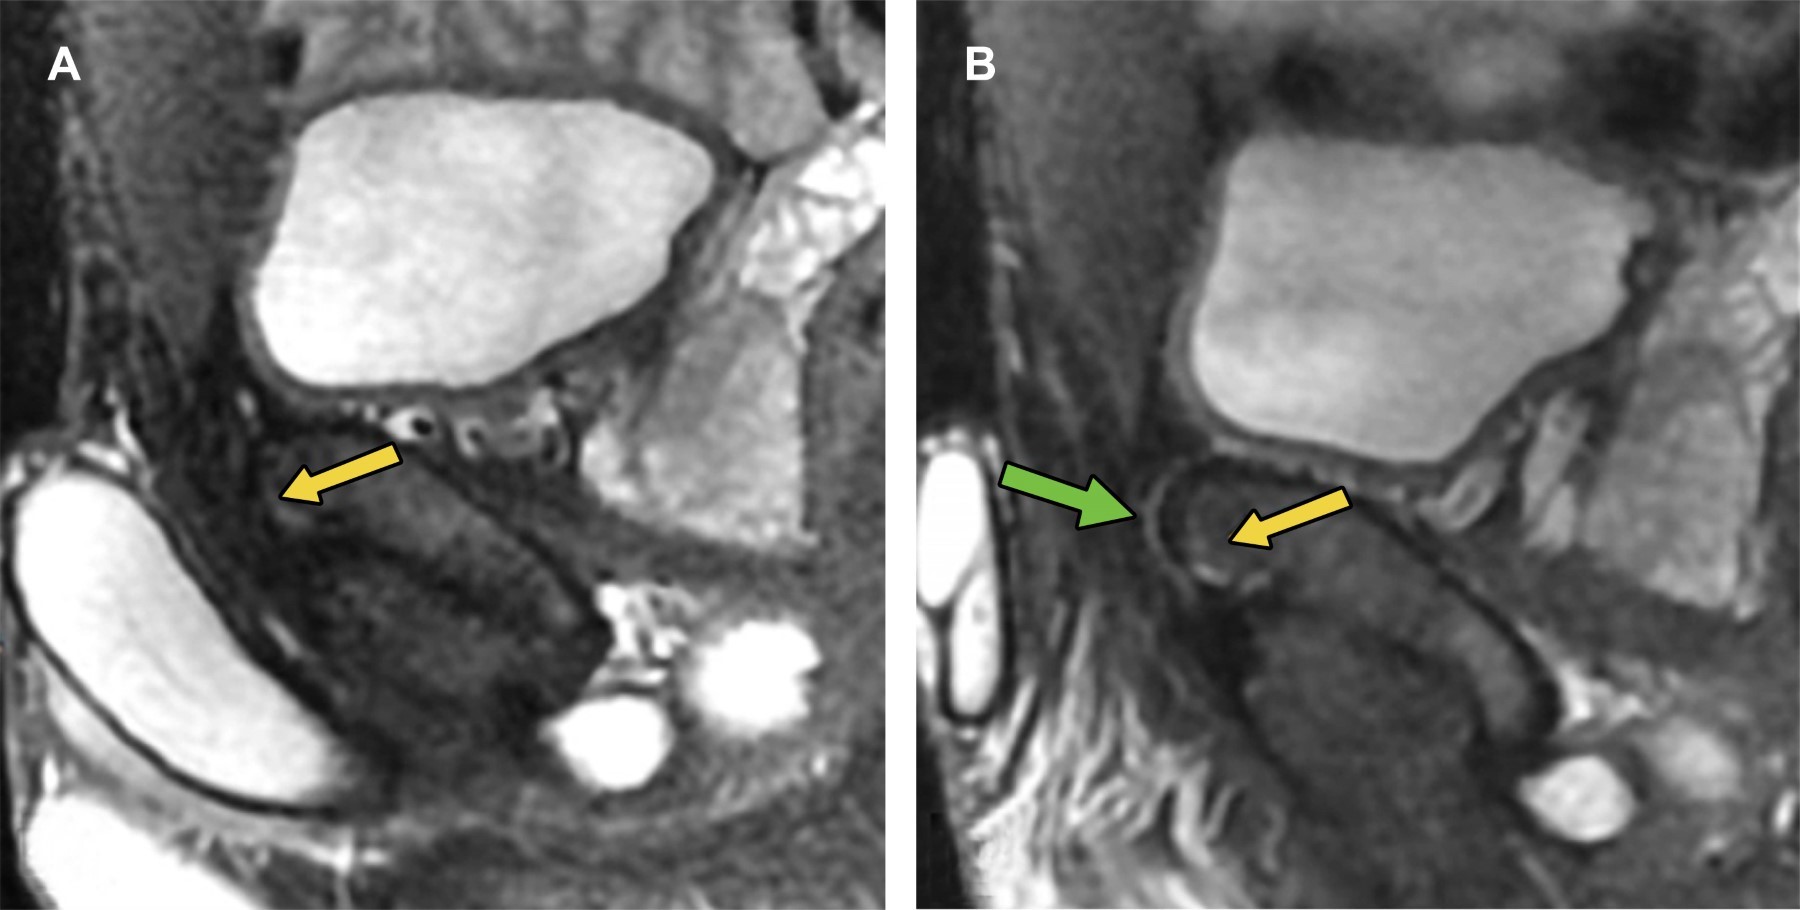

Athletic pubalgia is a clinical syndrome characterized by chronic inguinal pain secondary to muscle, tendon, or bone injury at the pubic bone level. It is a confusing diagnosis because there is a wide spectrum of pathologies that cause inguinal pain, and the clinical picture is nonspecific. In these patients, the magnetic resonance imaging (MRI) study plays a fundamental role in providing an accurate diagnosis.

Figure 3